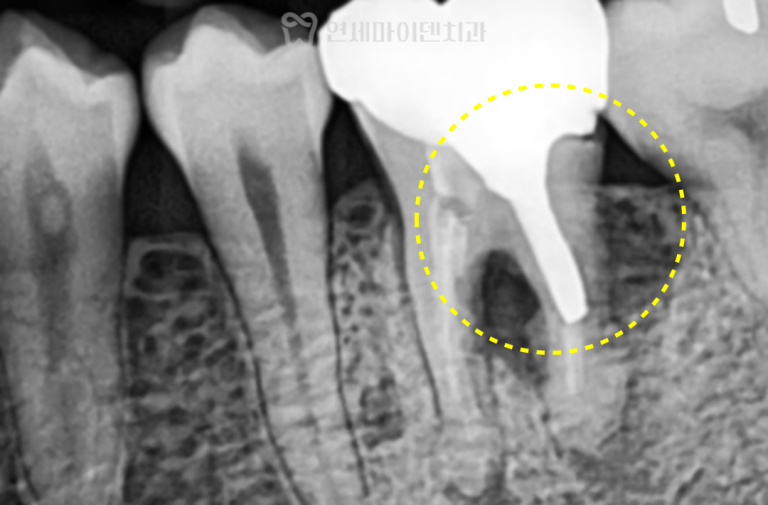

첫 번째 치아 치료 전

첫 번째 치아는 왼쪽 아래 어금니였으며

과거에 신경치료를 받은 상태였습니다.

내원 당시 잇몸에는

여드름처럼 보이는 고름 주머니가 있었고,

영상 검사에서 뿌리 끝을 중심으로

치조골이 까맣게 녹아 있는

J자 형태의 염증 소견이 관찰되었는데요.

이런 염증 양상은 일반적으로

크랙이 동반된 경우 의심이 되지만,

육안으로는 크랙이 직접적으로 보이지 않았습니다.